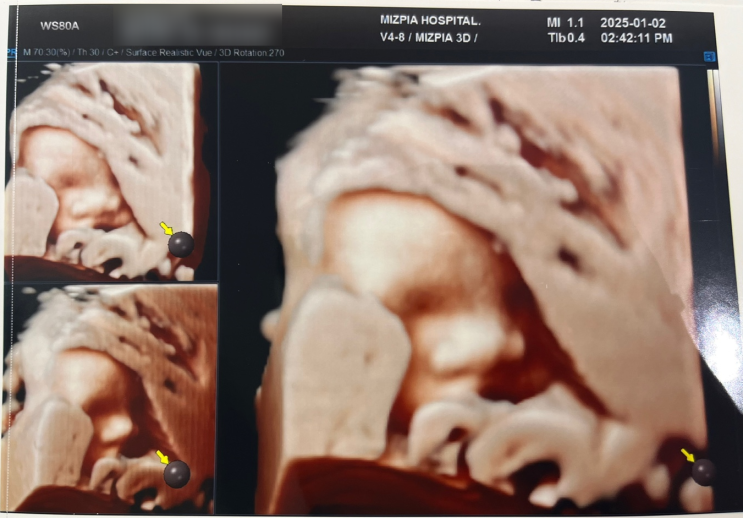

[임신일기] 30주차 정기검진 (30주2일)

새해맞이 한방이 보러가기 1월 2일 점심시간 직후 예약이라 사람이 없는듯 많은듯 했다. 필수코스인 머리길...